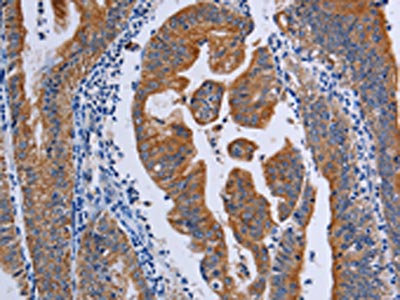

The image on the left is immunohistochemistry of paraffin-embedded Human gastic cancer tissue using CSB-PA196351(ACP6 Antibody) at dilution 1/50, on the right is treated with fusion protein. (Original magnification: ×200)

The image on the left is immunohistochemistry of paraffin-embedded Human prostate cancer tissue using CSB-PA196351(ACP6 Antibody) at dilution 1/50, on the right is treated with fusion protein. (Original magnification: ×200)